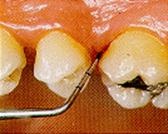

Código

3: bolsa patológica de 3,5 a 5,5 mm. o más, el área negra de la

sonda se encuentra a nivel del margen gingival.